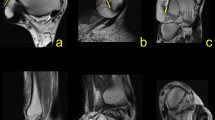

We found connections between the os trigonum and PTFL, PTCL, OF-FHL, paratenon and FTCL, and FR both in the experimental and control group (Table 1). The connections have the form of narrow, partly communicating fiber bands in both groups. The ligament most commonly connected to the os trigonum was the PTFL (Table 1 and Fig. 1). In most cases of the experimental group, the posterior part of the PTFL inserted on the os trigonum (n = 89, 85.6%), while in 10 (9.6%) cases, the whole PTFL inserted on the os trigonum (Fig. 1). In five (4.8%) cases of the experimental group, the PTFL inserted only on the posterior process of the talus, and no attachment to the os trigonum was noticed (Fig. 1). In all cases in the control group, the PTFL inserted on the posterior process of the talus (Table 1).

Three variants of the insertion of the PTFL. PD-weighted—a–c 1a—anterior part of the PTFL inserts on the talus; 1b—posterior part of the PTFL inserts on the os trigonum; 2—the PTFL inserts only on the os trigonum; 3—the PTFL inserts only on the talus; 4—the FTCL; 4a—the inferolateral lamina of the FTCL; 5—the FHL runs directly on the articulation of the os trigonum

The PTCL was identified in 98 (94.2%) cases of the experimental group, of which in 54 (51.9%) cases inserted on the os trigonum, while in 44 (42.3%) cases, it inserted on the posterior process of the talus (Fig. 2). No clear PTCL was noticed only in 6 (5.8%) cases of the experimental group. In the control group, the PTCL was noticed in 94 (90.4%) cases (p < 0.001), while no clear ligament was seen in the remaining 10 (9.6%) cases. An accessory projection from the PTCL to the posterior outline of the joint capsule was noticed in 37 (35.6%) cases of the experimental group. Posterior to the os trigonum, a "fibrotic node-like structure" (Fig. 3) was visible in 41 (39.4%) cases vs. 43 (41.3%) cases in the control group (p > 0.05). The surrounding structures received fibrotic projections from fibrotic node-like structure (Figs. 2 and 3).

The connection to the OF-FHL (Fig. 4) was seen directly in 44 (42.3%) cases or through the fibrotic node (Fig. 3) mentioned above in 23 (22.1%) cases of the experimental group. FHL runs in most cases at the level of articulation between the os trigonum (n = 66, 63.5%), followed by the posterior process of the talus (n = 26, 25%) (Fig. 1) and less often on the os trigonum (n = 12, 11.5%) (Fig. 5).

The FTCL is a delicate thin fibrous lamina set in the frontal plane located between the os trigonum (n = 93, 89.4%) or the posterior process of the talus in the experimental group (n = 95, 91.3%), p > 0.05), medial and lateral malleolus and paratenon posteriorly. At the insertion on the lateral malleolus, the FTCL connected to the calcaneofibular ligament in 4 (3.8%) cases in the experimental group and in 9 (8.7%) cases in the control group (p < 0.05). The connection between the os trigonum and superior peroneal retinaculum via the FTCL was seen in 31 (29.8%) cases of the experimental group (Fig. 5). The FTCL prolonged medially into the FR in 89 (85.6%) cases in the experimental group and 91 (87.5%) cases in the control group (p > 0.05). The os trigonum was connected to the paratenon via the FTCL more often from the lateral side (n = 33, 31.7%) compared to that in the medial side (n = 6, 5.8%). The corresponding values in the control group were generally higher (n = 67, 63.8%, p < 0.001) for the lateral side compared to those in the medial side of the paratenon (n = 31, 29.5%, p < 0.01). The medial expansion of the FTCL connected with the plantaris tendon in n = 57 (54.8%) in experimental group in while in control group (n = 52, 50%, p > 0.05). The plantaris tendon was connected directly to the paratenon in (n = 19, 18.2%) cases in the experimental group and in (n = 23, 22.1%) cases in the control group (p > 0.05). The absence of a connection of the plantaris tendon with ligament projections included in the study was noticed in (n = 28, 26.9%) in the experimental group and (n = 29, 27.9%, p > 0.05) in the control group.

The connections of the os trigonum with neighboring structures are located within KFP (Fig. 6).

a Prominent connections of the os trigonum, PD sequence. b General map of the communications between different fibrotic structures at the level of the os trigonum. 1—PTFL, 2—connection to the osteo-fibrosus tunnel of the FHL, 3—FTCL, 3a—branch of FTCL to the os trigonum, 4—connection to the Kager’s fat pad